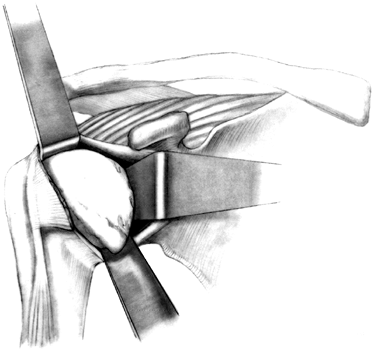

dislocation of the humeral head before osteotomy. -

Dislocate the humeral head by gently

extending and externally rotating the arm and placing a blunt elevator

between the humeral head and the glenoid. Take care with osteopenic

bone, as in rheumatoid arthritis, because the shaft can be fractured

during dislocation of the head. The humeral head is now ready for

osteotomy (Fig. 101.25).

Figure 101.25.

Dislocate the humeral head, place the retractors superiorly and

inferiorly, and identify the marginal osteophytes. (From Craig EV.

Total Shoulder Replacement for Primary Osteoarthritis and

Osteonecrosis. In: Craig EV, ed. The Shoulder. Master Techniques in Orthopaedic Surgery. Philadelphia: Lippincott Williams & Wilkins, 1997:18, with permission.) -